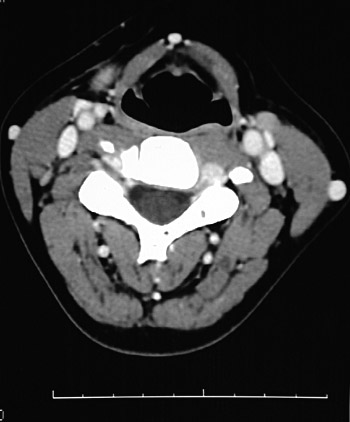

This is a normal axial head and neck CT scan demonstrating the thyrohyoid membrane and pharynx and sternocleidomastoid muscle and external jugular vein and levator scapulae muscle and semispinalis muscle and splenius capitis muscle and trapezius muscle and internal jugular vein and common carotid artery.